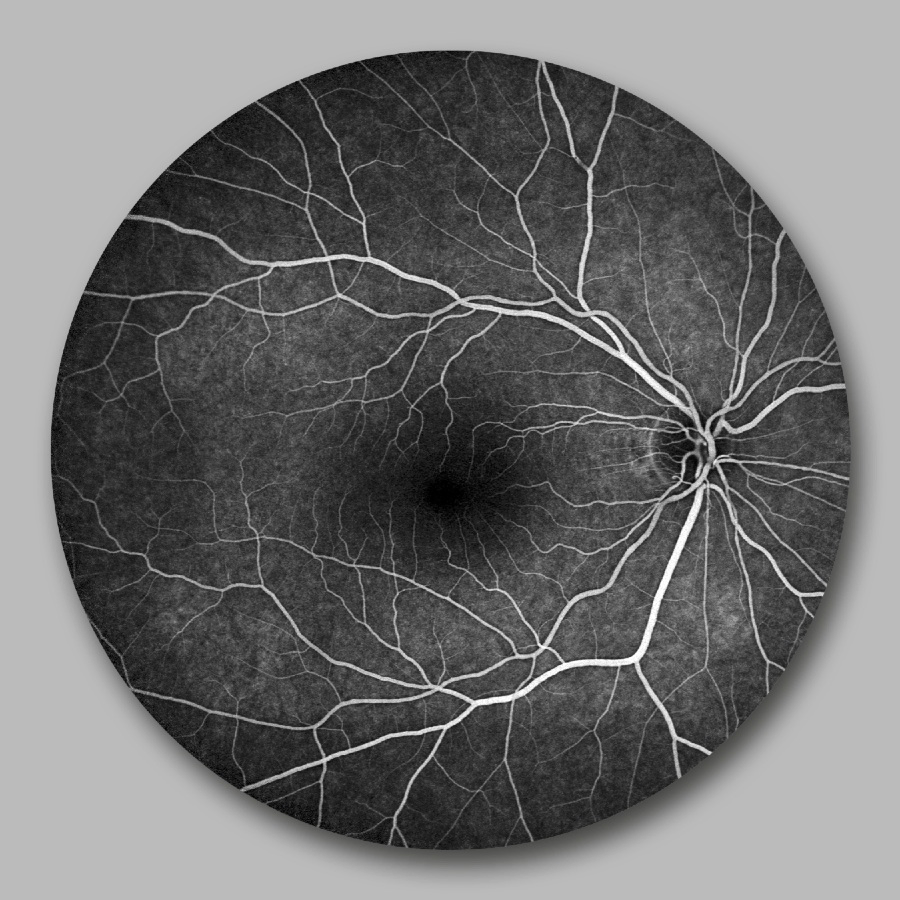

Rétine saine: angiographie en fluorescence

06

03